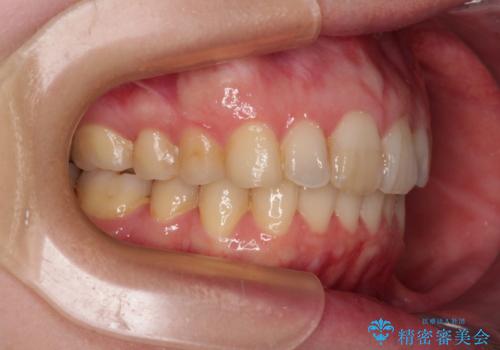

- 上顎前歯の突出感と、前歯のクロスバイトを気にして来院された患者様です。

前歯の叢生と口元の閉じにくさを気にして来院された患者様です。

奥歯の咬み合わせを見ると、上顎が下顎に対して相対的に前方にありました。

カリエール・ディスタライザーを用いたことで上顎前歯の突出感はスムーズに解消され、歯列不正は1年半ほどでほぼ改善することができました。